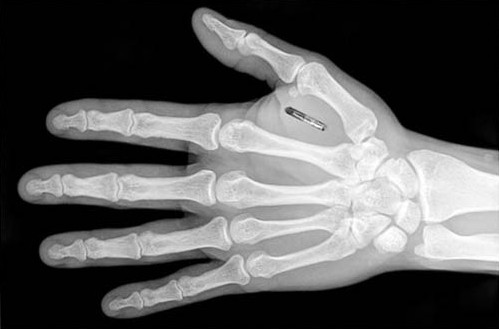

但是現(xiàn)在,曾在電影中出現(xiàn)的場景,曾被我們認(rèn)為是天方夜譚的事情正在我們的現(xiàn)實社會中一一實現(xiàn)。一些特工電影里超酷超炫的場景,就像隨便握握手就可以實現(xiàn)文件的傳輸之類的都在慢慢的變?yōu)楝F(xiàn)實?,F(xiàn)在看來在身體中植入芯片看似前衛(wèi)看似瘋狂,但是在不久的將來,它肯定會遍及我們周圍。就好像我們可以在手機中植入信用卡,為什么我們就不可以把柔性電路板芯片植入身體中呢?

早在1998年的時候,有個名叫凱文·沃維克的教授就往自己的左臂中植入了一個硅片脈沖轉(zhuǎn)發(fā)器。后又在2002年往自己的左腕中植入了一個3毫米的方形芯片,該芯片可以連接100個電極,可以讓自己的神經(jīng)系統(tǒng)與計算機相連。據(jù)說在他的辦公大樓的所有智能設(shè)備都能識別出他,可以隨著他的動作自動開門、開燈、關(guān)門,而且他的電腦可以自動發(fā)出問候,并在收到新郵件時直接通知到他。

在很多的電影和小說中,一個被植入芯片的人一般都會脫離普通人的行列,成為一個“超人”。這個芯片可以控制疾病、可以延長壽命、可以遠程操控武器或者是電腦、甚至還可以控制其他人的思想。但是,目前最現(xiàn)實的問題是,現(xiàn)在的芯片植入技術(shù)還沒有成熟,電池fpc技術(shù)也還沒有跟上,所以芯片植入還只存在于實驗室中,并未普及。據(jù)報道,有些用于醫(yī)療的植入芯片對患者產(chǎn)生的副作用,比如惡心、不規(guī)則出血等。所以這些芯片必須要經(jīng)過更多的試驗和改進才能真正面世。